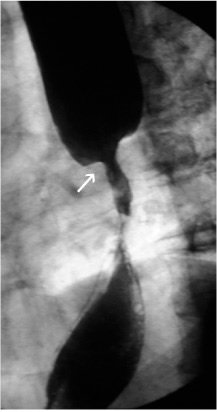

A visão endoscópica de prótese recoberta após colocação (esquerda) mostra a patência da prótese no estudo contrastado (direita).

Os pacientes com estenoses malignas de alto grau mais frequentemente apresentam doença avançada.

O objetivo da colocação de prótese é:

- atravessar a obstrução no esôfago

- permitir, primariamente, a patência luminar para:

- controle da saliva

- ecundariamente, para nutrição.

Próteses auto-expansíveis e flexíveis são construídas em duas camadas de uma superliga de fio monofilamentar, com uma camada de silicone entre ambas. O silicone interposto às camadas retarda o crescimento tumoral através dos orifícios do aramado.

Após a administração de anestesia local ou geral, a estenose é dilatada a 42 ou 45 French, a lesão é identificada, e a prótese recoberta e expansível é colocada sob controle endoscópico e fluoroscópico. Uma vez que a prótese é inserida e expandida, os rebordos são ancorados à parede esofágica.

Os pacientes percebem desconforto torácico inicial pela distensão da estenose. A inserção de próteses metálicas auto-expansíveis não impede tratamento posterior com quimioterapia ou radioterapia. Apesar da melhora do paciente em deglutir saliva, a ingestão oral deve se restringir a alimentos que passam através de uma prótese esofagiana rígida.

A média de sobrevida após a colocação de uma prótese para carcinoma esofágico é inferior a 6 meses.